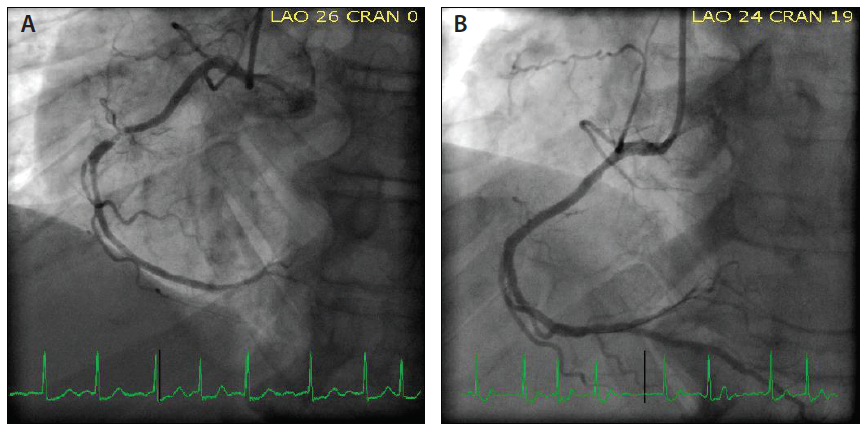

Using a 6-F Railway™ sheathless access system and a 6-F Judkins right (JR) 4 Launcher® guide (Medtronic), the right TRA was obtained (Figure 2A). After getting direct guide catheter access in the RA, the Railway™ dilator was removed and the catheter was connected to the manifold using a Y-connector. Vasodilator cocktail (nitroglycerin 100 mcg + verapamil 2.5 mg) was injected through the manifold (Figure 2B). RA angiography was performed because of difficulty in advancing a 0.035-inch J wire, which showed severe tortuosity in the RA originating from the axillary artery (Figure 3A). A 0.018-inch V-18™ ControlWire™ (Boston Scientific Corporation) was advanced through the tortuosity(Figure 3B). A JR 4 guide catheter was advanced using a 0.018-inch Railway™ dilator without any resistance (Figure 3C) under direct fluoroscopic guidance to the right subclavian artery. The 0.018-inch wire and Railway™ dilator were removed. The JR 4 guide was cannulated in the right coronary artery (RCA). The mid-RCA subtotal occlusion (Figure 4A) was treated with a 1.5- X 20-mm balloon, followed by 3- X 15-mm and 3- X 15-mm Cobra PzF™ stents (CeloNova BioSciences, Inc.) to treat the 95% to 99% stenosis in the mid-RCA and 70% stenosis in the mid/distal RCA, respectively, with a very good final angiographic result (Figure 4B).

Figure 2. A 6-F, 0.018-inch Railway™ dilator is preloaded with a guide catheter, and direct guide catheter access is obtained over a 0.018-inch access wire in the RA (A). An example of a guide catheter in the distal RA after direct catheter access, and an intra-arterial vasodilator cocktail is injected using the manifold (B).